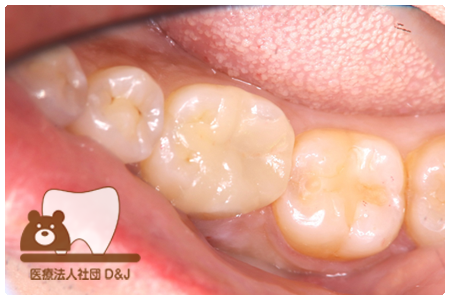

症例3フリジルコニアクラウン 左上6

治療前

治療後

59歳 男性

- 治療内容

- 虫歯で大きく失われた歯に対して、土台としてファイバーコアを使用し、その上にフルジルコニア製の被せ物を装着しました。見た目と強度を両立した自由診療の治療です。

- 治療期間

- 根の治療含めて3カ月半

- 費用

- 自費

フリジルコニアクラウン:77,000円(税込)

(R8.2月時点)

- その他の治療の費用は含まれておりません。

- リスク・副作用

- 強い力が加わると割れる可能性があります。また、噛み合わせや歯ぎしりの影響で脱離することがあります。